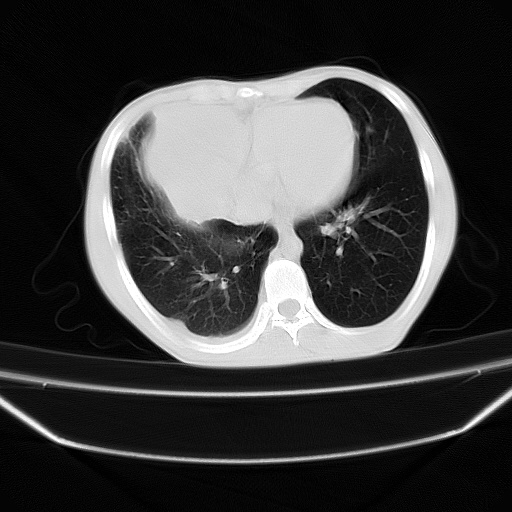

以下是引用zjzjr在2008-7-20 12:57:00的发言:[br]考虑为生殖源性肿瘤(内胚窦瘤),侵袭性胸腺瘤可能性大;右侧少量胸腔积液。

以下是引用xinliheng001在2008-7-20 21:17:00的发言:[br]右纵隔巨大分叶状软组织均质密度肿块,右上肺叶受压明显,纵隔右移、胸膜受累有少量积液和结节样增厚。应增强扫描一定会有更具诊断价值的信息。

以下是引用xinliheng001在2008-7-20 21:17:00的发言:[br]右纵隔巨大分叶状软组织均质密度肿块,右上肺叶受压明显,纵隔右移、胸膜受累有少量积液和结节样增厚。应增强扫描一定会有更具诊断价值的信息。